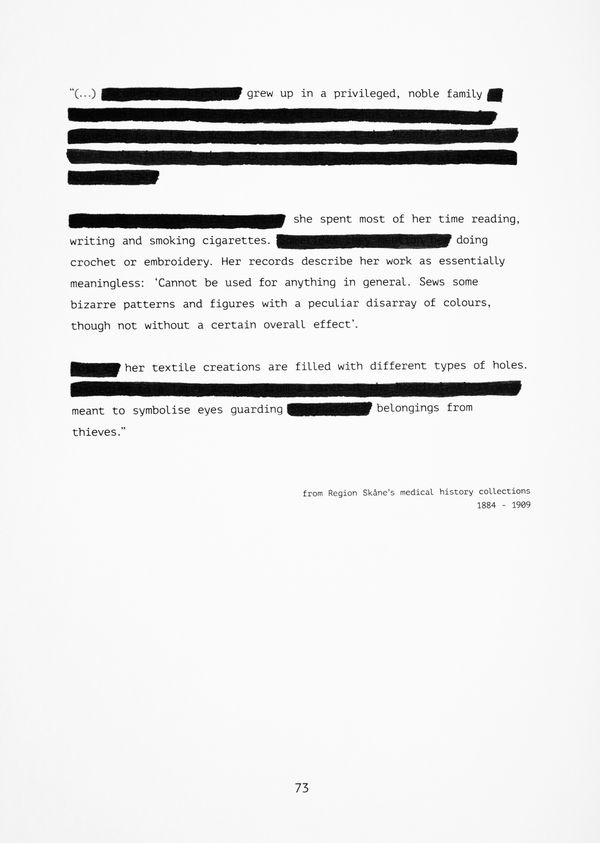

Inspired by the missing archive of her life's work, I began tracing other histories of women whose textiles speak where records fall silent, continuing the intergenerational legacy of weaving scraps into stories.

With the use of archival images and documents, staged compositions, and photographic interventions printed and layered through textile processes, the work is a reconstruction based on multiple (hi)stories stitched together: those of women makers, of rebels, and those whose voices were recorded, devalued, or lost.